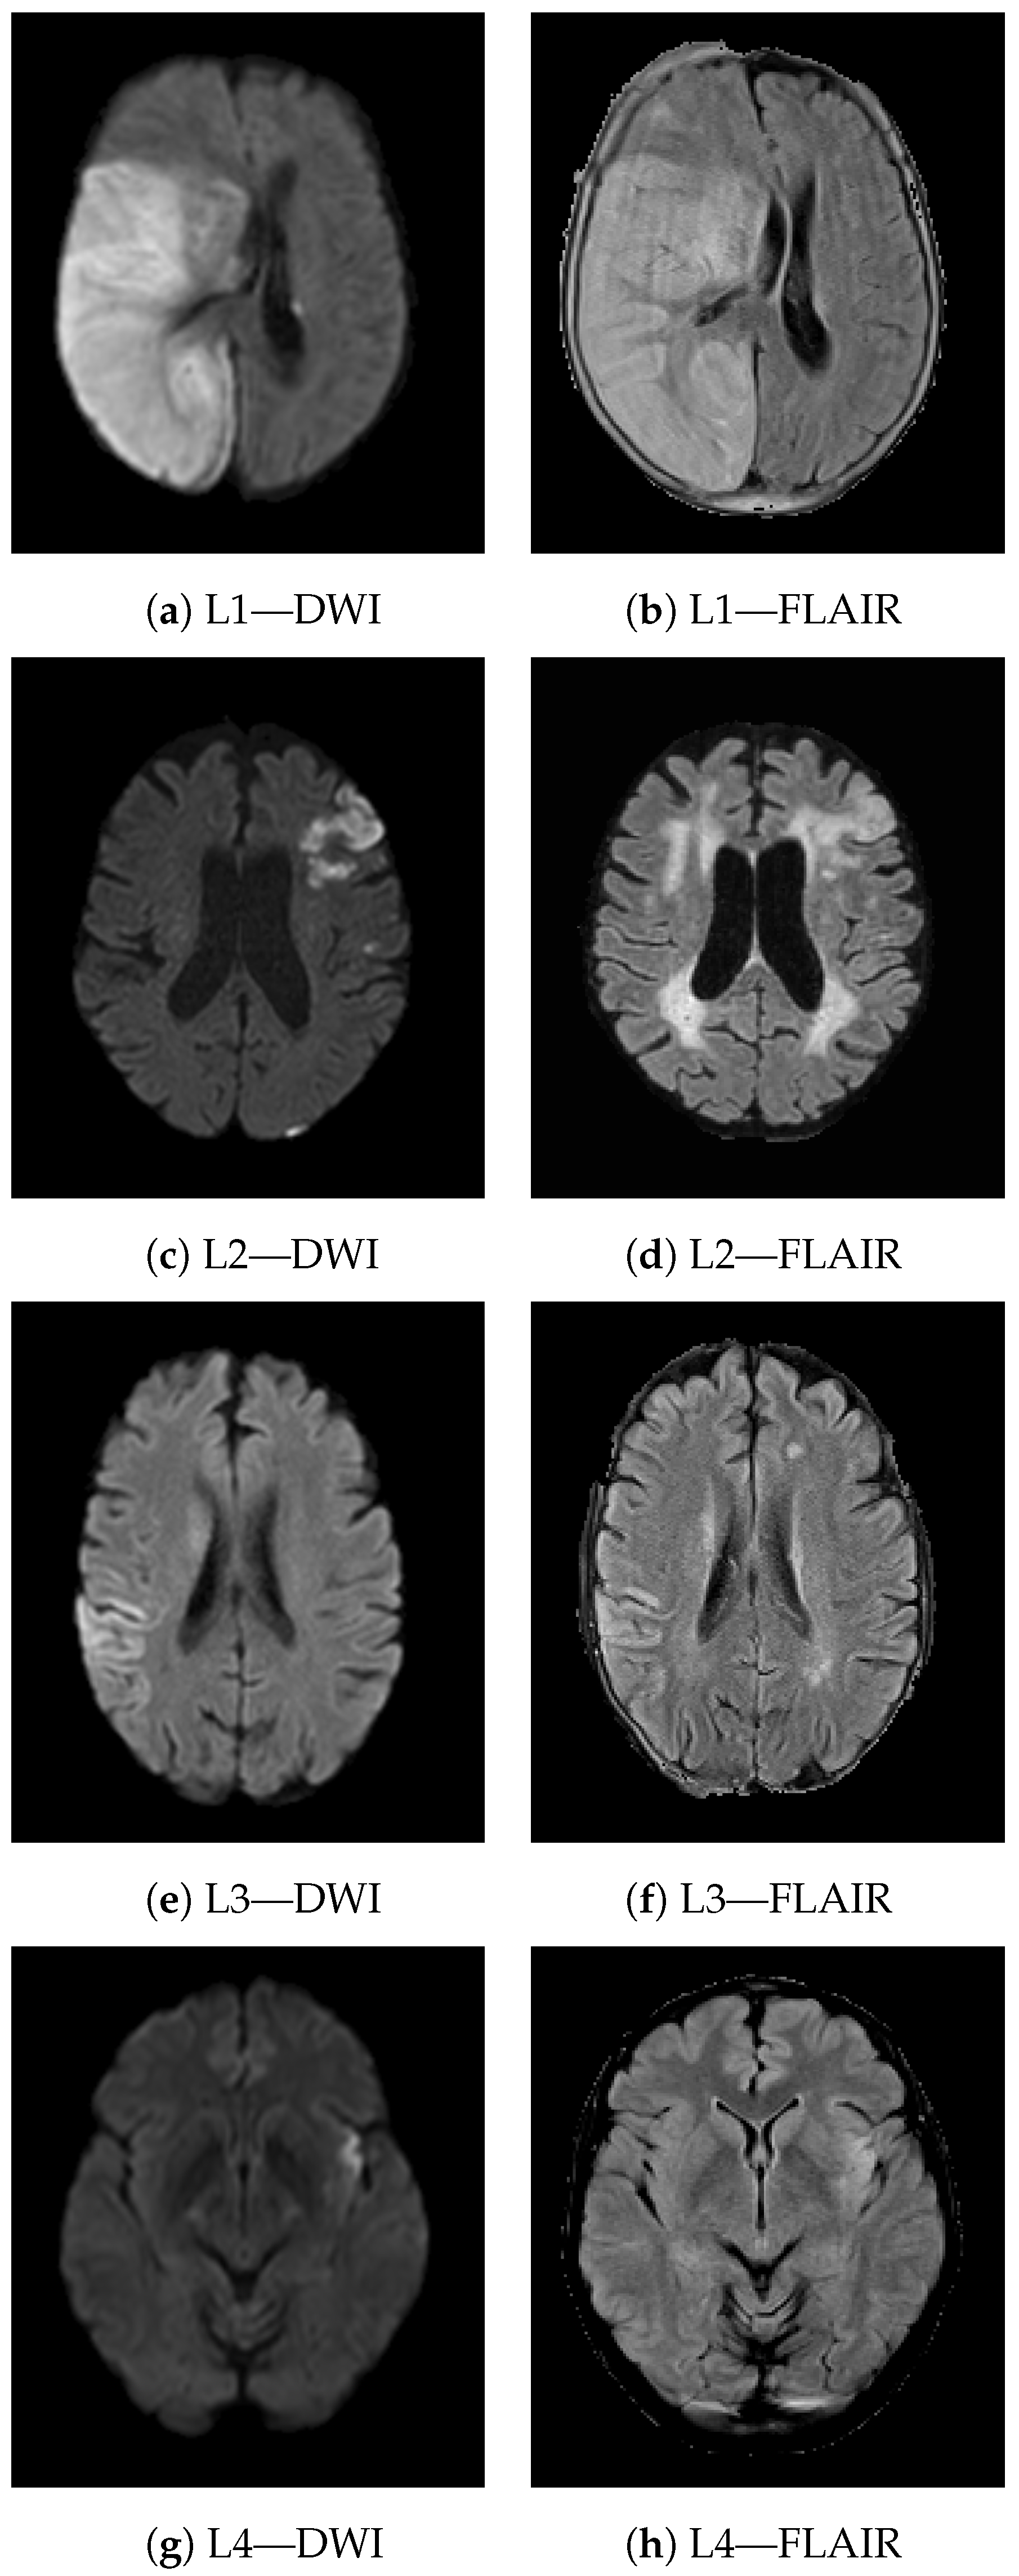

2.2. Image Preprocessing